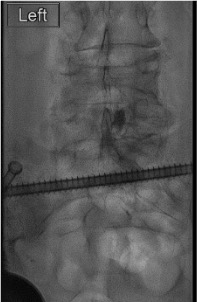

Contrast injection — "Christmas tree"

Inject steroid + anesthetic